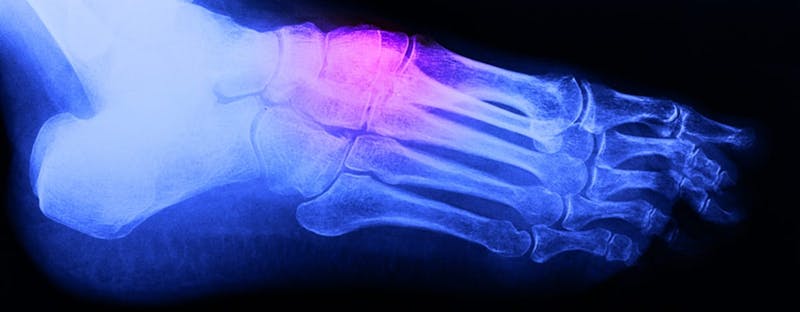

The foot is comprised of 26 bones that, in spite of their relatively small size, do a remarkable job of supporting our weight and getting us from place to place. An accident or trauma can crush, twist, bend, or otherwise fracture these bones. The following looks at the most common types of foot fractures and how they are treated.

Metatarsal Fractures

The metatarsals are the longer bones at the base of each toe. A fracture of the first metatarsal, which is attached to the big toe, may require a cast, surgery, and crutches. A fracture of the middle three metatarsals usually responds well to partial weight-bearing and a rigid flat-bottom shoe. The fifth metatarsal, which is attached to the little toe, is the most frequently fractured bone in the midfoot. There are two basic types of fractures that affect the fifth metatarsal: